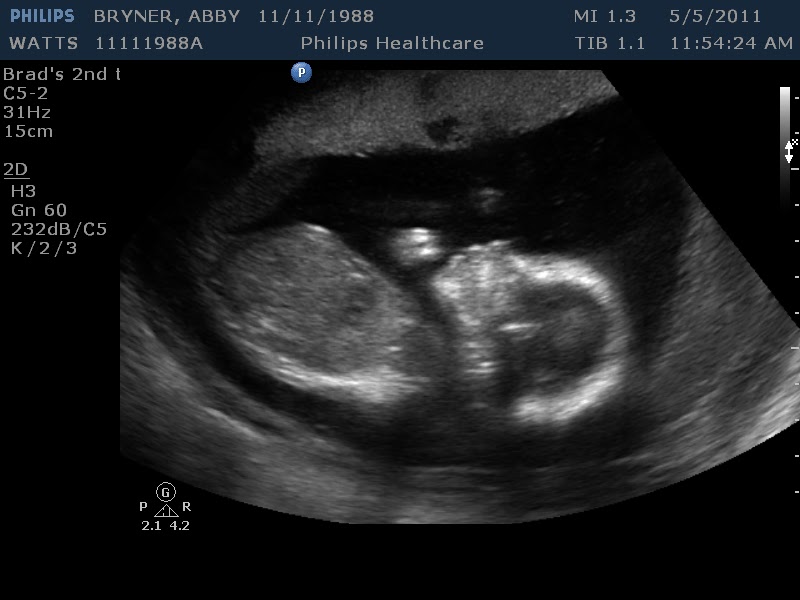

Source: smellaylt.pages.dev Foetus at 20 weeks, 3D ultrasound scan Stock Image C038/8813 Science Photo Library , It checks on the physical development of the fetus and can detect certain congenital disorders as well as major anatomical abnormalities What is the 20-week ultrasound? A 20-week ultrasound, sometimes called an anatomy scan or anomaly scan, is a prenatal ultrasound performed between 18 and 22 weeks of pregnancy

Source: techeahil.pages.dev 20 Week 3d Ultrasound change comin , What is the 20-week ultrasound? A 20-week ultrasound, sometimes called an anatomy scan or anomaly scan, is a prenatal ultrasound performed between 18 and 22 weeks of pregnancy The 20-week ultrasound can help show the health of the pregnancy and the developing fetus